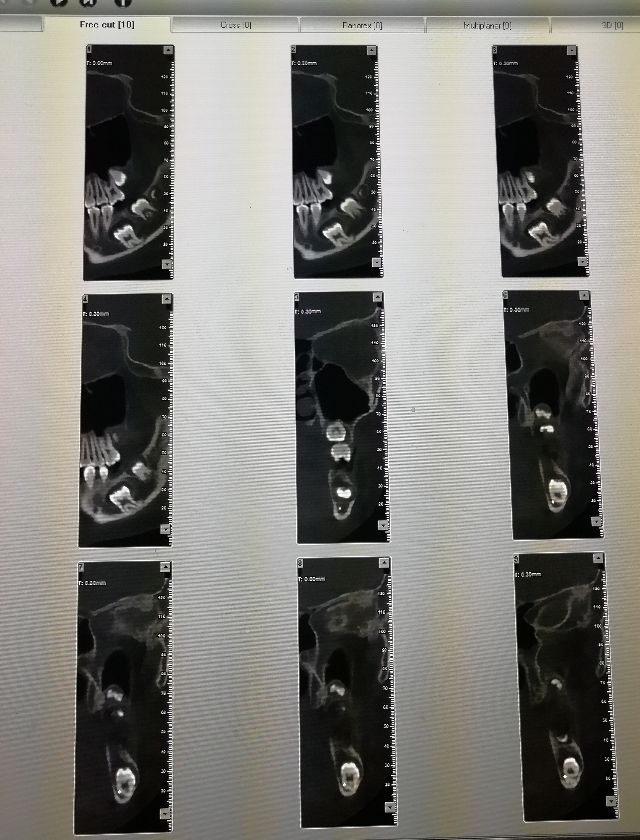

口腔检查:左下六龄牙(36)未萌出,其它3个六龄牙均正常萌出建合。

放射检查见片: 处理:局麻下拔除36

1.36如此低位不萌,原因不明,有待探讨。

3.拔除36:拔除后通过正畸方法保留间隙,将来修复(可以种牙)或移动其它牙齿关闭间隙。弊端:手术有一定风险,可能伤及下牙槽神经,出现下唇麻木症状。利端:相对简单,避免牵引治疗可能出现的牙财两空局面。

4.暂不处理,观察:该牙根尖已闭合,牙冠囊肿已形成,没有萌出潜力,留置后囊肿发展变大,无异于养虎为患。